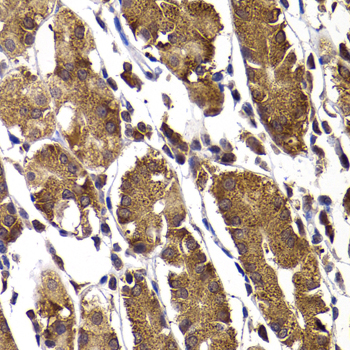

Immunohistochemistry of paraffin-embedded human stomach using STAMBP at dilution of 1:100 (40x lens).